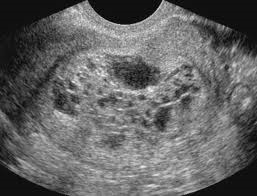

Lehetőség van a kombináció a terhesség és a méh mióma. Diagnosztikai támogatás ebben az esetben az a felfedezés a petesejt során ultrahang vizsgálat a kismedencei szervek és a kimutatási a vér vagy vizelet humán korion gonadotropin.

Estrogenprodutsiruyuschie petefészek daganatok (Tecoma, follikulomy) kísérik jelenségek hyperestrogenia megnyilvánuló gyűrűs vérzés szülőképes korú nők, akik korábban szabályos menstruációs ciklust. Méh jelenlétében az ilyen tumorok enyhén növekszik, és egy sima felületű. A vizsgálat egyik petefészkek mozgatható, sűrű konzisztenciát gömb vagy ovális alakú duzzanat a láb, amely gyakran kell különböztetni subserous myoma csomópont a szűk bázis. Diagnózis útján ultrahang, laparoszkópia, radiológiai kutatás feltételeinek pneumoperitoneum.